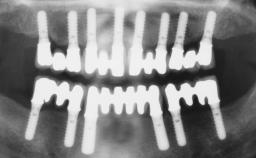

Immediate Loading of Four Implants in the Mandible and Final Restoration with a Full-Arch Metal Framework FDP

Pedro Tortamano, Luiz Otávio Alves Camargo

A fully edentulous 65-year-old woman was referred to our clinic for esthetic and functional dental rehabilitation. The patient presented with inadequate complete maxillary and mandibular prostheses, insufficient vertical dimension, and extensive tooth wear. The clinical examination and anamnesis showed no local or systemic contraindications, no signs or symptoms of bruxism, and an absence of smoking habits. The treatment proposed was implant placement in the mandibular interforaminal area and immediate loading with a fixed definitive prosthesis. A removable mucosa-supported complete prosthesis was indicated for the upper jaw, since its bone structure offered satisfactory retention and the financial condition of the patient disfavored a full-mouth implant-supported rehabilitation.

# of Implants 4

Type of Implants One-Piece

Attachment One-Piece

Prosthesis Type FDP

Loading Protocol Immediate

Retention Screw-retained, with 4 or more splinted implants Screw-retained, with 4 or more splinted implants